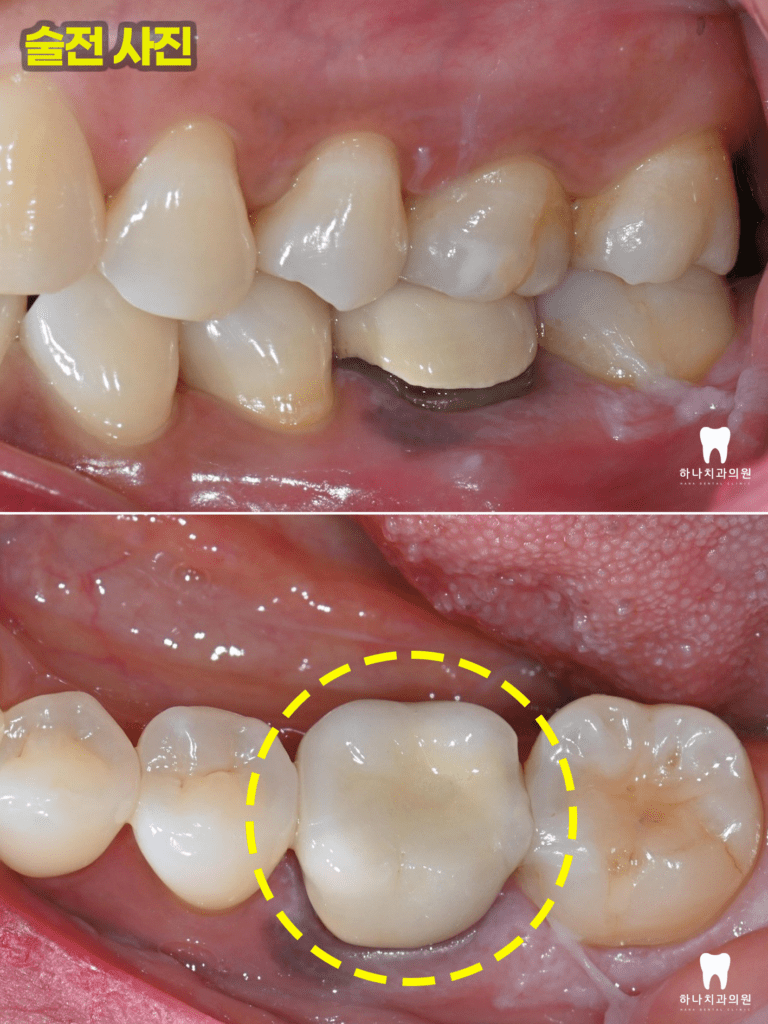

먼저 기존의 크라운을 제거하고

재신경치료를 시작하였는데요.

재신경치료는 성공률이 50%가 되지 않고

뚜껑에 해당하는 크라운을 제거했을 때

건전한 치질이 부족 시 그마저도 시도하지 못하는

경우가 발생할 수도 있으며

통증이 더 심해질 수도 있는 여러 사항을 말씀드리고

최후의 방법으로 환자분의 동의를 얻고

시작하였습니다.

이미 충전된 3개의 근관 충전물을

모두 제거하고 처음 치료 당시

찾지 못했던 숨은 근관도 1시간

넘는 시간을 들여 찾아내었습니다.

첫날 한 시간 반이 넘는 시간 동안

묵묵히 견뎌주시고 저는 손가락에

물집을 얻었습니다.

4회에 걸쳐진 치료를 완료하고

근관의 완전한 확보, 세척, 충전을

완료한 뒤 마무리 후 본뜨기 전의 모습입니다.